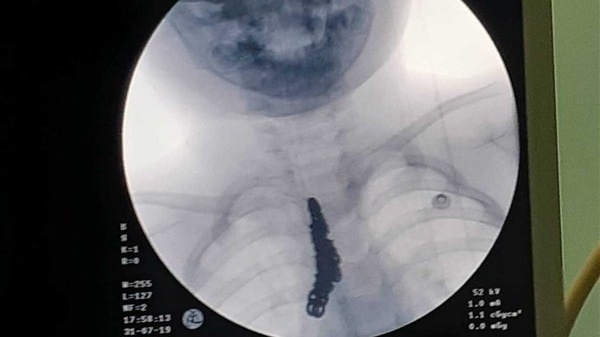

| Hình ảnh nội soi dạ dày bệnh nhân cho thấy que tăm đang nằm ngang dạ dày. (Ảnh: BVCC). |

Sau khi siêu âm, các bác sĩ xác định bệnh nhân này bị nhiễm trùng dạ dày. Trong quá trình nội soi, bác sĩ CKI Hồ Văn Khiêm - Khoa Nội (Bệnh viện đa khoa TP Hà Tĩnh) phát hiện trong dạ dày bệnh nhân có dị vật nằm ngang. Khi bơm rửa sạch thì đó là một que tăm, các bác sĩ sau đó đã soi gắp que tăm ra khỏi dạ dày cho người bệnh.